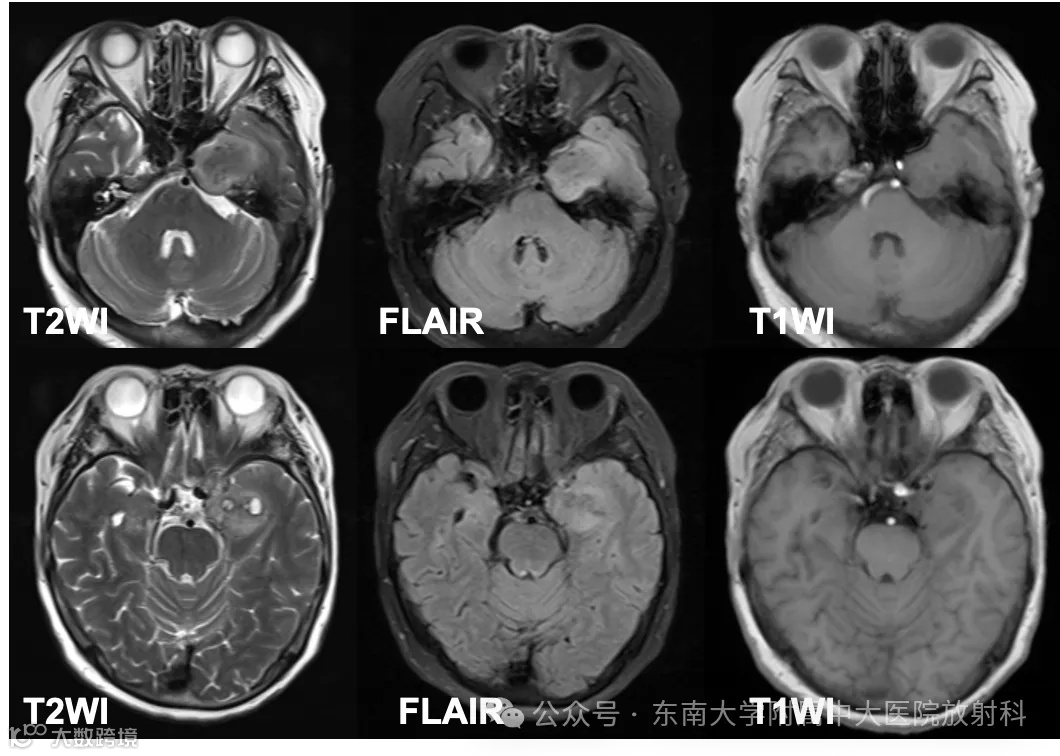

性别:女 年龄:69岁

主诉:左侧面部麻木5年余,加重伴肿胀1月余

现病史:患者5年前出现无明显诱因左侧面部麻木,至当地医院检查发现左侧鞍旁占位,予定期复查,未予特殊处理。1月前患者出现左侧面部麻木伴肿胀阵发性加重,遂至当地医院查头颅MR示:左侧鞍旁肿瘤,33x29mm,较前增大,多发陈旧性腔隙性脑梗死。头颅CT示:颅底介入术后改变。现患者为求进一步诊治至我院就诊,门诊拟“左侧鞍旁占位性病变”收住入院

既往史:自诉4年前于当地医院行脑动脉介入栓塞术

影像学表现